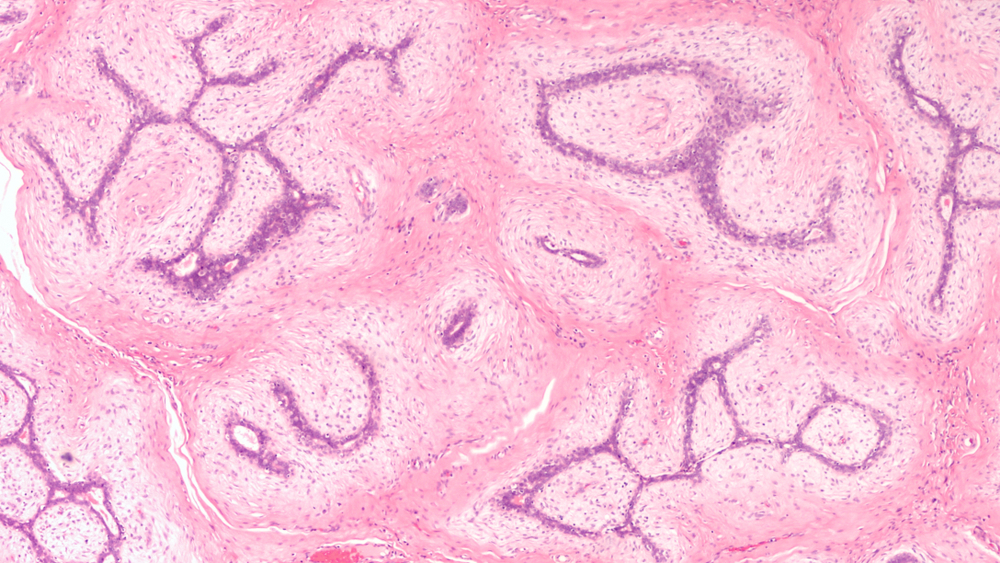

Vědci uvádějí, že pokud se nádory rozšíří do hlavních krevních cév, mohou vyvolat srážení krve, které přispívá k selhání orgánů.

Proto někteří lidé s pokročilou rakovinou umírají rychle, zatímco jiní přežívají, i když se rakovina rozšířila po celém těle. Vzorky krve také odhalily prudký nárůst počtu rakovinných buněk v krevním řečišti těsně před smrtí.